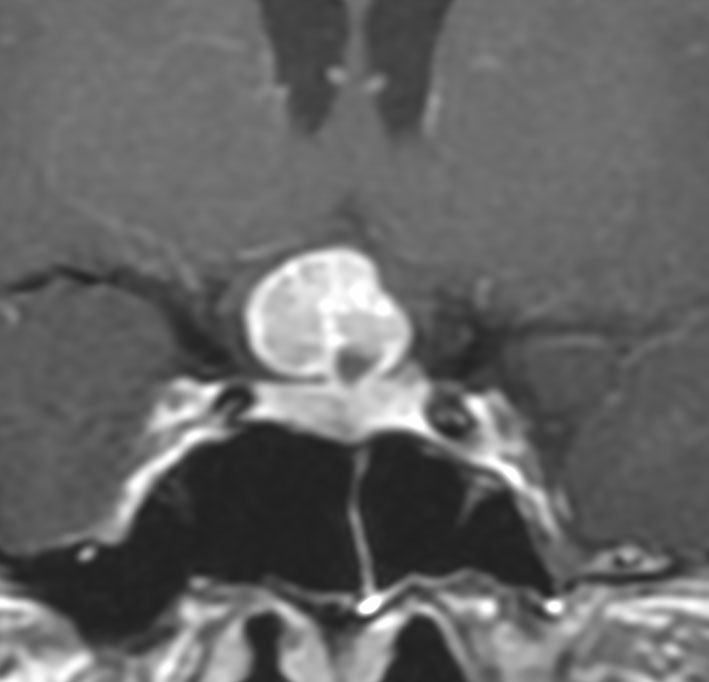

40代の女性に,軽度の両耳側半盲で発生したものです。視交叉と視床下部の下面に腫瘍があり,下垂体柄の位置が全くわからず,下垂体の前葉と後葉は侵されていません。ですから,下垂体柄から発生した腫瘍であり,pituicytomaが強く疑われます。T2ではほぼ等信号,小さなのう胞があり,ガドリニウムで強く増強されます。手術では正常下垂体柄の一部が右側にうすく残っており,幸運にも亜全摘出できて下垂体機能は温存できました。残存腫瘍は増大傾向を示していません。でも,このようなタイプを積極的に摘出すると,汎下垂体機能低下症を招くことが多いので,手術するかどうかの判断はとても難しいです。

下垂体後葉腫瘍の典型的な画像です。下垂体柄(黄色の矢印)が伸びて前方へ偏移しています。またその直下に下垂体前葉(強い白の部分)がみえます。

ジャーミノーマでは下垂体柄も同時に太くなるのでジャーミノーマは否定的な所見です。

- 画像上は境界が明瞭な腫瘍です

- 腫瘍内部にvascular voidsが多く見えて激しく出血する腫瘍です

- トルコ鞍内から発生することが多いと記載されていますが,実際は灰白隆起か下垂体柄からの発生が多く,鞍上部腫瘍となります